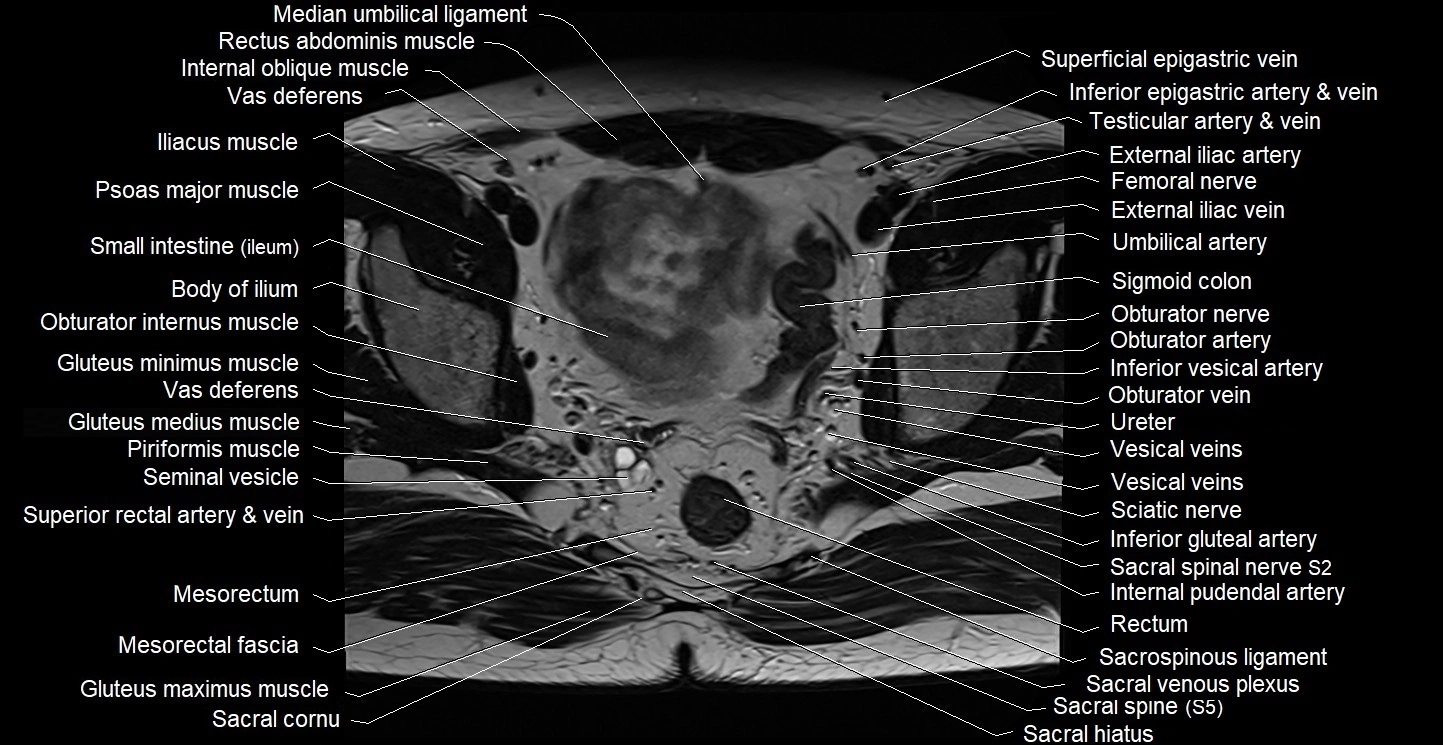

- Anal canal

- Body of ilium

- Common iliac vein

- External anal sphincter

- External iliac artery

- External iliac vein

- Femoral nerve

- Gluteus maximus muscle

- Gluteus medius muscle

- Gluteus minimus muscle

- Internal anal sphincter

- Internal iliac artery

- Internal iliac vein

- Internal oblique muscle

- Median umbilical ligament

- Mesorectal fascia

- Mesorectum

- Obturator artery

- Obturator internus muscle

- Obturator nerve

- Obturator vein

- Piriformis muscle

- Psoas major muscle

- Puborectalis muscle

- Rectum

- Sacral plexus

- Sacrospinous ligament

- Sciatic nerve

- Seminal vesicle

- Sigmoid colon

- Small intestine

- Spinal nerve S1

- Superior gluteal artery

- Superior rectal artery

- Superior rectal vein

- Umbilical artery

- Vas deferens

- Vesical veins